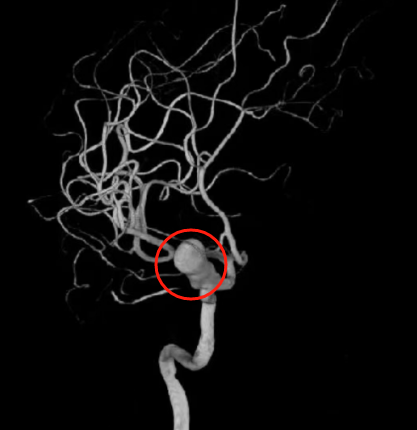

随后,医生对张文进行头颅CT血管造影扫描,证实出血的原因是颈内动脉眼动脉段动脉瘤破裂出血。其中动脉瘤大小25×12 mm,属于巨大动脉瘤。

检查发现巨大脑动脉瘤

术中,李主任凭借精湛的技术和经验,巧妙引导血流改变方向,从而有效阻止动脉瘤的进一步膨胀和破裂风险。手术顺利完成,造影显示动脉瘤栓塞致密,瘤腔不显影。术后第3天张文可下床活动,四肢运动、语言功能等均正常。“他整个人都轻松了,还能愉快地和医生护士聊家常。”家属笑说。